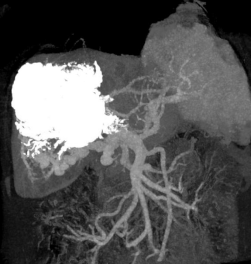

该患者是一位56岁女性,连续两年反复呕血、黑便、腹痛、腹胀。两年前在当地医院诊断为肝包虫病术后复发,门静脉闭塞合并门静脉高压,食管静脉曲张破裂出血。经内镜下多次治疗后仍反复呕血,伴有腹痛、腹腔积液。后经推荐至我院吴浩教授消化介入团队就诊。2023年8月,患者入院后增强CT显示门静脉主干完全闭塞,广泛门静脉重度海绵样变性,食管下段-贲门部静脉曲张,肝内多发巨大包虫病灶。

本例患者肝内外门静脉全程闭塞,导致严重门静脉高压和反复静脉曲张破裂出血,多次内镜治疗后效果不佳,因此需要手术降低门静脉压力才能有效预防再次出血。但患者肝实质存在较多包虫复发病灶,门静脉条件差,无论是再次外科手术切除、外科肠-门搭桥(rex分流)还是行传统的经颈静脉肝内门体分流术(TIPS)、经皮门静脉成形均存在手术禁忌。消化内科、肝脏外科团队对患者CT影像资料及临床检查进行仔细研究和评估后认为,只有经肠系膜上静脉门体分流术(TEPS)既能降低门静脉压力,又能避开包虫病灶,是患者目前最佳的选择。

(左图:术前CT重建 右图:术后CT重建)